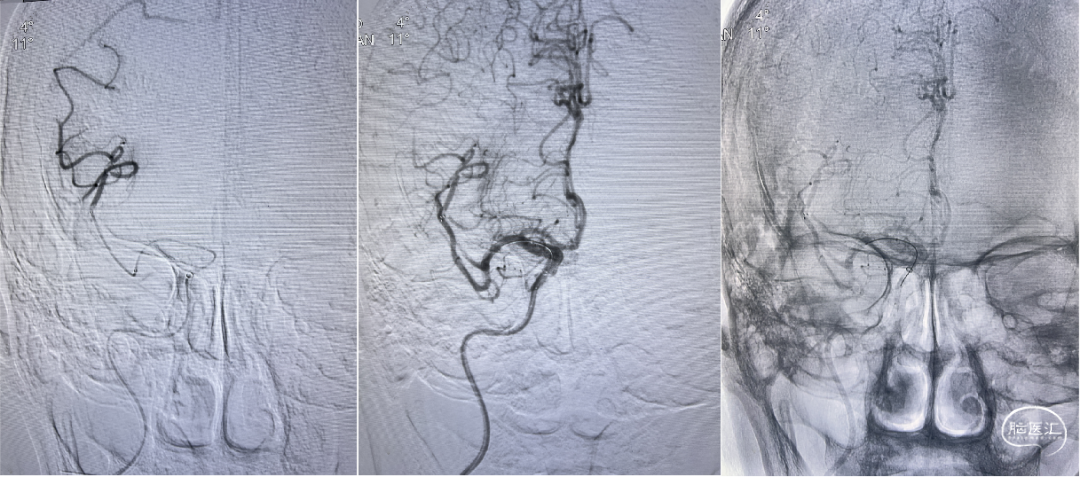

FlowGate 2同轴Catalyst 7、Synchro 2多次调整后穿过C1起始闭塞处,MicroPort Pioneer 2.5mm×20mm球囊C1起始处缓慢扩张,顺球囊Catalyst 7穿过闭塞段,继续向前推进FlowGate 2失败, Catalyst 7 C1抽吸出长条血栓。

Catalyst 7 C1抽吸出大负荷血栓。

Catalyst 7再次通过闭塞处于C2-C4近端抽吸,再无血栓抽出,球囊辅助通过(BTA)技术无法将CAT7带入C4远端,CAT减容任务完成,使用Solitaire FR 6×30支架行完整BADDASS技术, 6×30支架前行张力非常大,释放时并无法顺利推出Rebar 18微导管,导致支架释放略近于预期位置。

支架释放位置不理想,而且前行过程中导致血栓前移,支架并未覆盖血栓头端,经验告诉我们,仅靠软膜支的独立系统可能会通过BGC的血流阻断弥补前向压力(P),远端未覆盖血栓可能会因为血栓之间的粘附力而一并拖出。

充盈FlowGate 2,CAT 7施加张力,希望CAT 7能在支架回撤过程中抓住血栓尾端,但CAT 7在虹吸弯纹丝不动,负压下同时撤出支架与DAC。

BADDASS技术下支架取出长条血栓,3D-DSA可见眼动脉下方重度狭窄,CAT 7在张力下的上行切割狭窄处,导致小夹层产生。